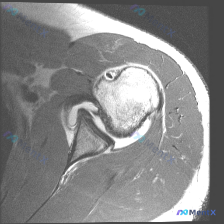

肩关节MRI现前盂唇异常信号,是撕裂还是解剖变异?

整理了一份肩关节MRI病例讨论材料,先放轴位T2加权像的分析。

核心发现:

- 扫描层面在盂肱关节中部,显示肱骨头、关节盂、前后盂唇

- 前盂唇(图像左侧)可见明显不连续高信号,穿透盂唇结构

- 后盂唇形态完整,信号均匀;肩胛下肌、肱二头肌长头腱未见明显异常

讨论焦点:这个前盂唇病变更像真性撕裂(如Bankart损伤)还是解剖变异(如盂唇下孔、Buford复合体)?大家第一反应怎么看?